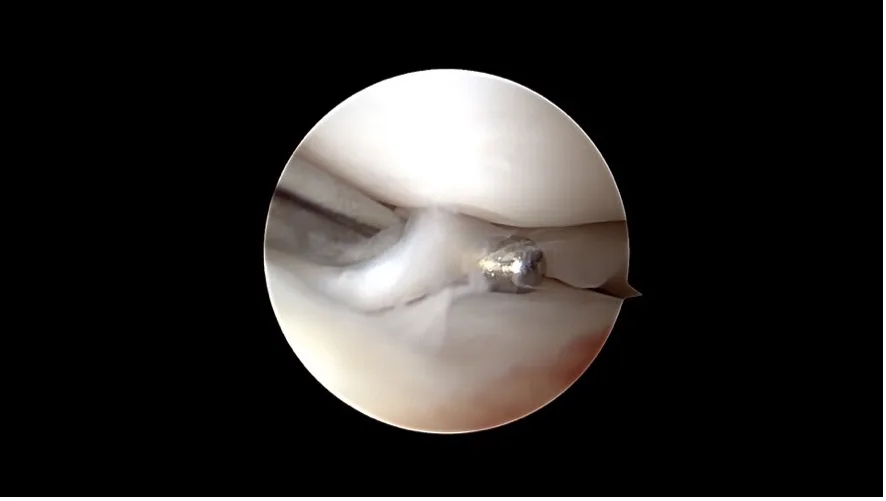

An incipient cruciate ligament tear is hidden beneath the remaining cruciate ligament, which appears unremarkable at first glance.

A complete cruciate ligament rupture

Nanoscopy

Even finer than arthroscopy, nanoscopy uses very small instruments and high resolution imaging inside the joint. It is particularly suitable for small dogs. Both methods are minimally invasive, cause less tissue trauma and support faster recovery.